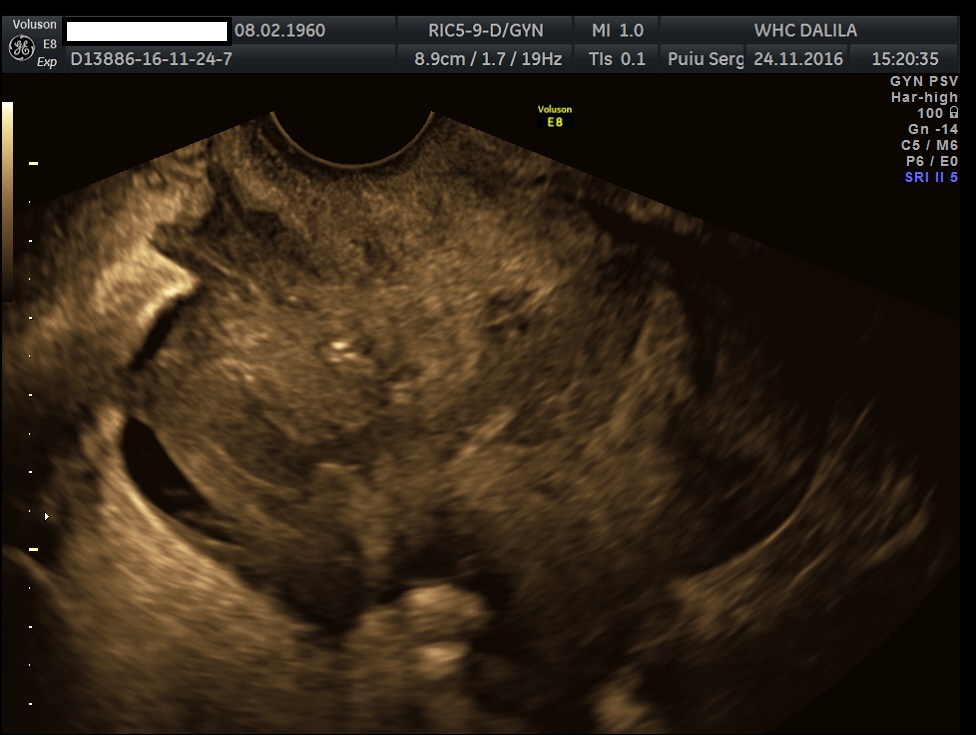

Transvaginal and transabdominal ultrasound scans were performed, which has shown the enlarged uterus with indistinct borders on the left side and a complex mass in left lower abdominal quadrant. A large irregular thick-walled, ill-defined multiloculated cystic/solid lesion with complex fluid collections and peripheral flow on color Doppler were seen. The anatomic distinction between the ovary and the fallopian tube could no longer be identified (Fig. 1). A tubo-ovarian abscess (TOA) was presumed. Endovaginal sonogram showed a dilated uterine cavity and cervical canal, filled with heterogeneous, complex fluid and echogenic masses (Fig. 2a-c). An intrauterine contraceptive was detected. A cavity within myometrium with low-level internal echoes fluid also was revealed (Fig. 2c). This complex adnexal mass was adherent to uterus and a communication between TOA and the cavity within myometrium with fluid-debris level fluid was detected (Fig. 3a-b). This finding presumed a perforation of the TOA into uterus, due to myometrium necrosis, and spontaneous drainages into uterine cavity through myometrium. Increased echogenicity of the pelvic fat and a small amount of free fluid in cul-de sac also were seen. Fluid movements through fistula canal between TOA and uterine cavity were clearly seen when a gently pressure by ultrasound probe was applied (Video 1).

Figures 3a-b. Transvaginal and transabdominal ultrasound scans. A complex adnexal mass adheres to uterus and a communication (fistula) between TOA and a cavity within myometrium and then into endometrial cavity with low level echoes fluid is clearly seen. Increased echogenicity of the pelvic fat and a small amount of free fluid in cul-de sac also can be seen.